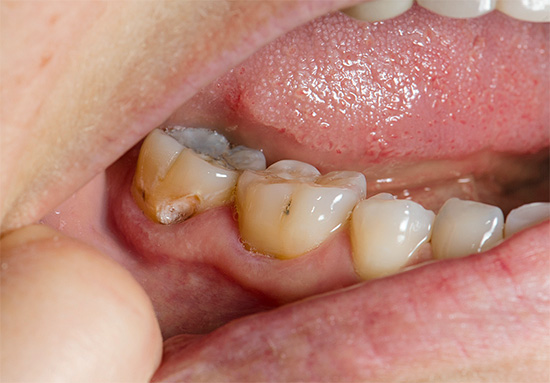

Foto de um dente com uma cárie profunda que atinge a câmara pulpar:

Objetivamente: após inspeção visual, determina-se uma cavidade profunda cariosa, preenchida com dentina amolecida e pigmentada, no quinto dente superior esquerdo (2.5). A parede de contato medial e a superfície mastigatória de 2,5 dentes são destruídas por um processo carioso. Na sondagem, é determinado o ponto de abertura da cavidade do dente, no qual a polpa é visível. Quando a sonda toca nesse ponto, a polpa sangra dolorosamente.

Geralmente, no dente, há uma cavidade profunda e cárie com dentina infectada amolecida, que freqüentemente se comunica com a câmara pulpar.Para esclarecer a presença dessa mensagem, o dentista usa uma sonda - um instrumento de metal curvo e afiado no final da sondagem.

O diagnóstico por raio-X também é importante. Na pulpite fibrosa crônica, uma cavidade profunda de cárie, que quase sempre se comunica com a câmara pulpar, geralmente pode ser observada na radiografia de um dente doente. Às vezes, uma ligeira expansão do espaço periodontal (o espaço entre a raiz e o osso dos alvéolos nos quais está fixado) é fixada.